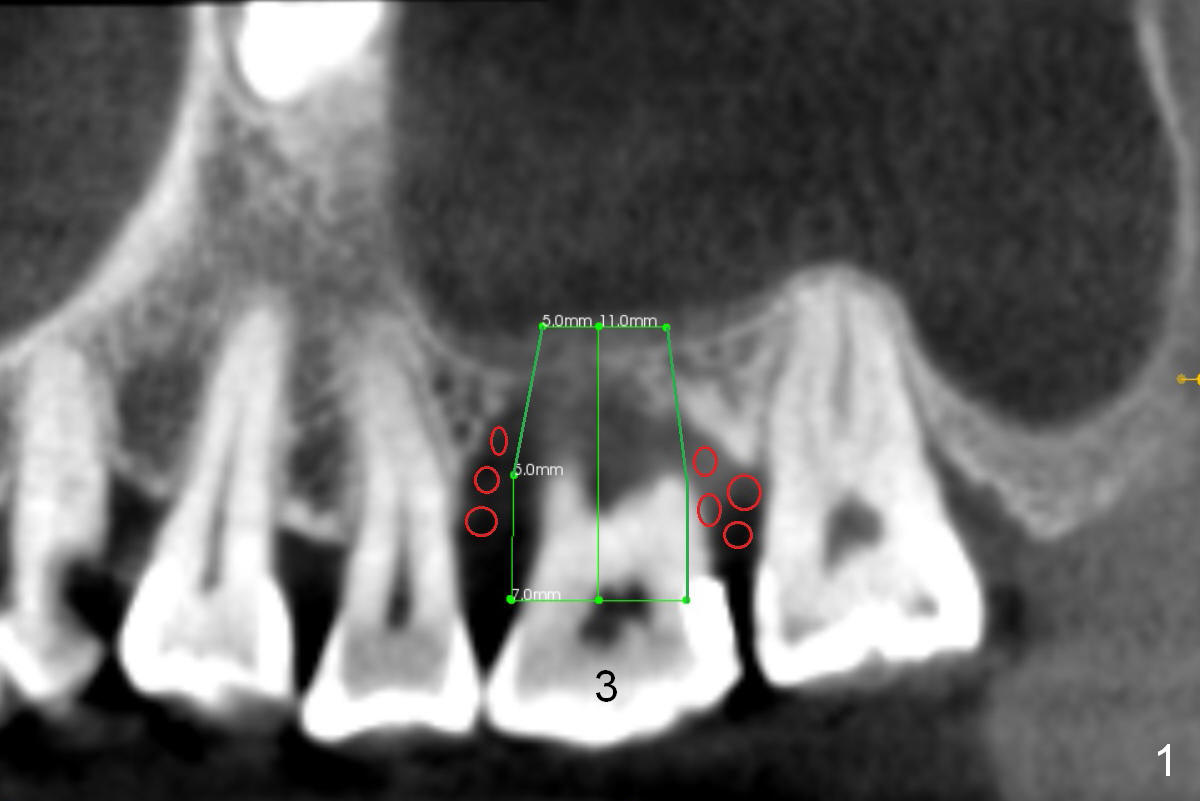

A 52-year-old lady (ZJ) has severe bone loss at #3 (Fig.1 (CT sagittal section)). After extraction, the socket will be treated with Metronidazole. A small amount of apical bone is available for primary stability; the bone density is also low (300-500 Hounsfield Units, Fig.3 (axial section)). Use RT2,3 for creating osteotomy and bone condensation, followed by 4.5-7x14 mm taps (11 mm deep; gingival margin). Prior to bone grafting (Fig.1,2 (coronal section) red circles), apply Endogain against the root surface of the neighboring teeth.